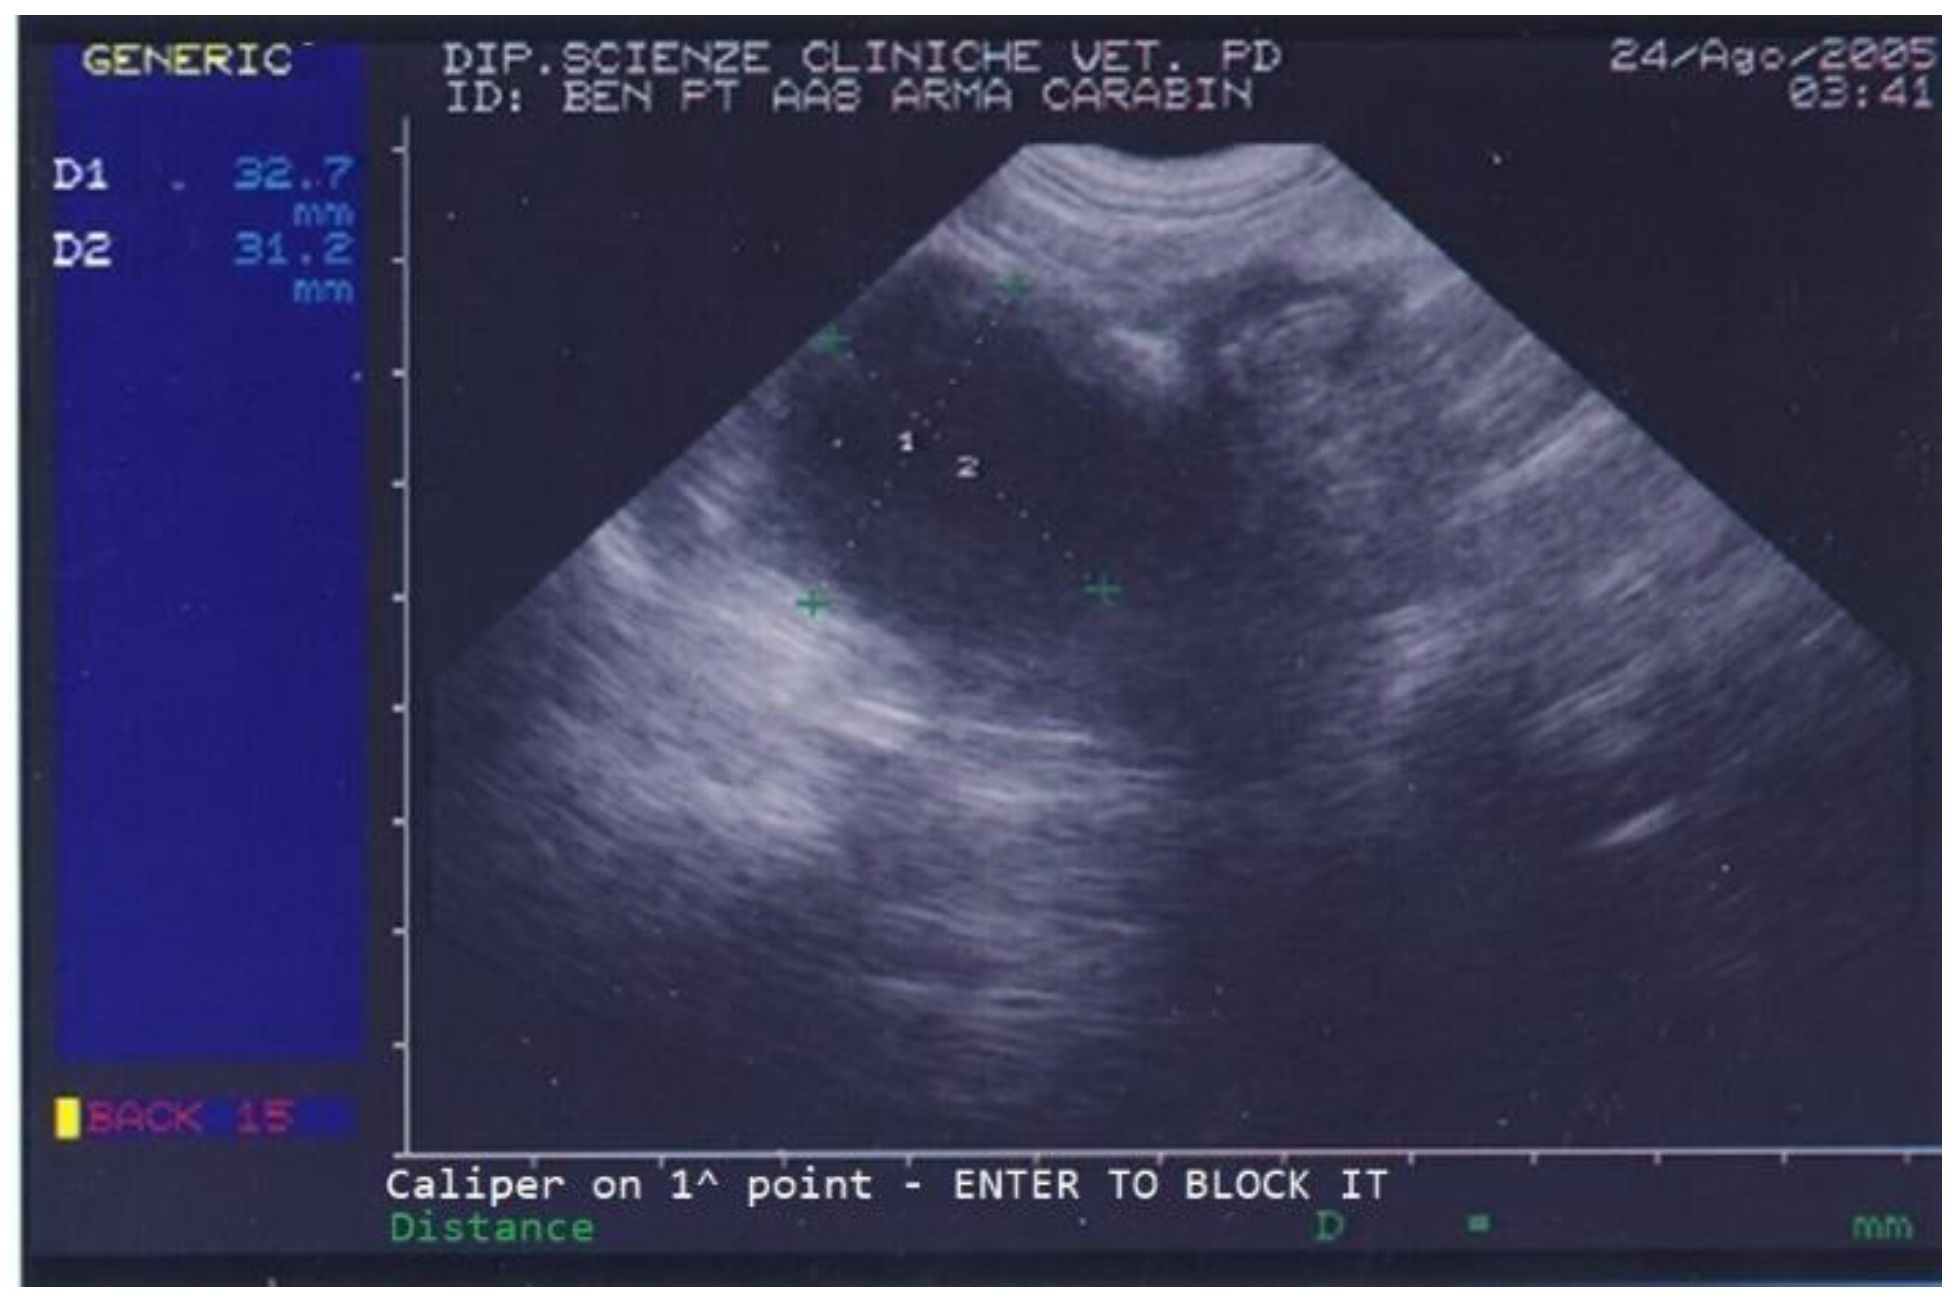

On the day of referral, the dog’s general conditions were normal, although he was underweight due to poor appetite, had normal skin (except for the left ear), normal subcutis and mucosal membranes, normal lymph nodes, and showed local alopecia and purulent ear discharge from his left ear. Abdominal palpation was unremarkable. On ultrasound, the dog’s prostate was increased in size and a few small cysts and a large (3.1 × 3.2 cm diameter) prostatic cyst were observed (Figure 1).

Figure 1.

Abdominal ultrasonography of a German shepherd dog before deslorelin implant. The scan shows the ultrasonographic appearance of the prostate. The largest prostatic cysts’ perpendicular diameters are measured as D1 = 32.7 mm and D2 = 31.2 mm.